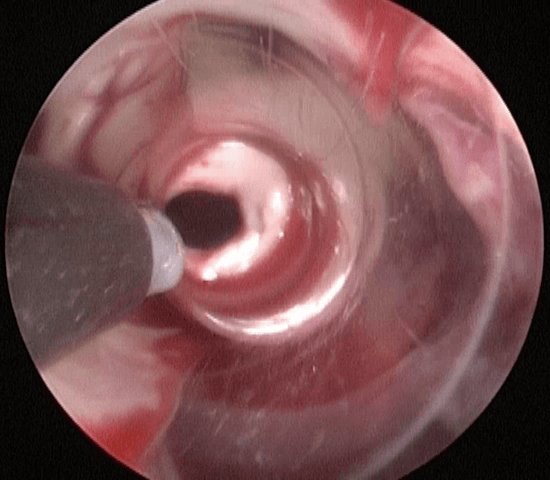

使用イメージ

[外径3.7㎜のシャフトで10mmのシースに対応]

[外径2.5㎜のシャフトで6mmのシースに対応]